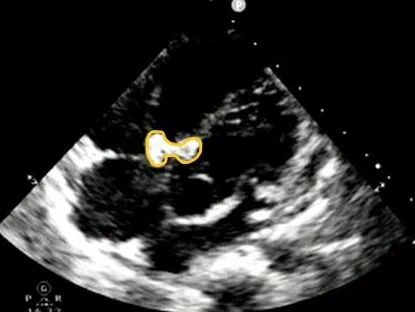

门诊心脏彩超提示:

超声多切面示:室间隔膜周部可见连续中断,局部不规则向右室膨出,呈“囊袋状”,断端回声增强,测缺口大小:左室面6.5mm、右室面2.5mm,隔瓣下残缘5mm,彩色血流示:室水平左向右分流,Vmax 473cm/s,Pgmax 89 mmHg。

各房室腔大小及大血管内径未见异常。各瓣膜厚度、弹性、开放幅度正常,彩色血流示:三尖瓣反流(少量),长度1.51cm、面积1.4cm2,容积1.0ml,Vmax 216cm/s,PGmax 16mmHg。据三尖瓣反流法估测肺动脉收缩压为28 mmHg;左室收缩功能正常,EF为74%。

术前超声与DSA复测

VSD(膜周部):室间隔膜部瘤,左室面6.5mm,右室面呈“瘤样”结构,瘤体深度7mm,出口2mm。

该病灶呈现为“长隧道、大瘤底、小出口”的细腰形态,且位置紧邻主动脉瓣与三尖瓣,解剖结构较为复杂。此形态特征使得可降解封堵器在植入过程中的定位与释放面临较大挑战。